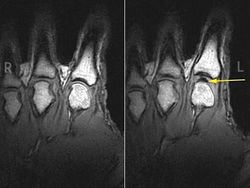

Полость в суставе за счет которой образуется характерный звук. Фото: University of Alberta

Почему трещат пальцы (МРТ запись)

Кавитация (или трибонуклеация) - образование небольших газовых полостей в суставе, которые способны резко увеличить объем внутрисуставного пространства. Исследования показали, что синовиальная жидкость содержит довольно много растворенного газа - диоксида углерода (примерно 15% от общего объема). И в 1947 году Wheeler Haines предположил (используя подтверждения, полученные с помощью рентгенограммы), что щелчок возникает вследствие резкого образования полости газа, которые создают возможность для внезапного расширения амплитуды движения, что и порождает звук. Однако с помощью скоростной камеры было показано, что пузырьки вновь спадаются через 0,01 секунду после возникновения. Позднее долгое время считалось, что спадение пузырьков газа служит причиной хруста сустава.[1] Поскольку не все пузырьки газа коллапсируют, необходимо некоторое время на его полное растворение (примерно 15 минут) в синовиальной жидкости, также время требуется для того чтобы суставные поверхности сблизились (только тогда возможен эффект кавитации). Например, при вытягивании пальца руки создается вакуум в пястно-фаланговом суставе, внезапно образуются полости газа, которые затем мгновенно спадаются, что и порождает вибрации, которые передаются окружающим тканям.

В 2015 году проведенное группой ученых МРТ-сканирование в реальном времени показало, что именно момент образования пузырьков в синовиальной жидкости вызывает щелчок, а их спадение происходит беззвучно.[2]